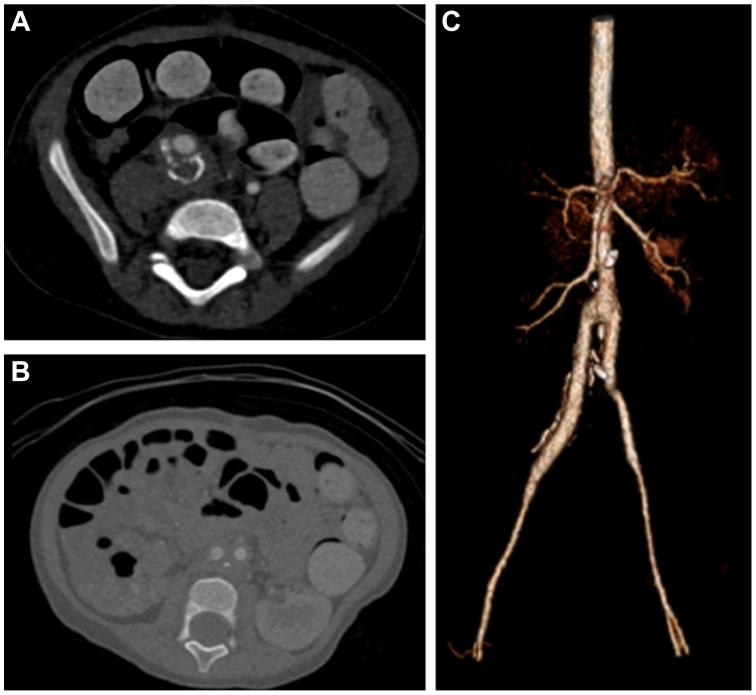

An abdominal aortic aneurysm (AAA) in children is a rare clinical condition, with idiopathic AAAs even more atypical. We report a case of a 19-month-old girl with incidental findings of an infrarenal AAA and right common iliac artery aneurysm during workup for heart failure. Extensive genetic testing was unremarkable for connective tissue disorders. An aortic bi-iliac artery bypass with a Dacron graft from the infrarenal aorta to the right external iliac artery and left common iliac artery was performed. The patient achieved complete recovery and only required one oral hypertensive medication at 30 days of follow-up. Wide patency of the graft was observed on the 3-month follow-up computed tomography angiogram.

儿童腹主动脉瘤(AAA)是一种罕见的临床病症,特发性AAA则更为罕见。我们报告一例19个月大女童,在因心力衰竭进行检查时偶然发现肾下腹主动脉瘤和右侧髂总动脉瘤。广泛的基因检测未发现结缔组织疾病相关异常。采用涤纶移植物进行了从肾下腹主动脉到右侧髂外动脉和左侧髂总动脉的主动脉双髂动脉搭桥术。患者完全康复,随访30天时仅需一种口服降压药物。在3个月的随访计算机断层扫描血管造影中观察到移植物通畅良好。